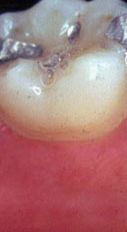

pase el ratón sobre las piezas para ver: bolsa, recesión y movilidad